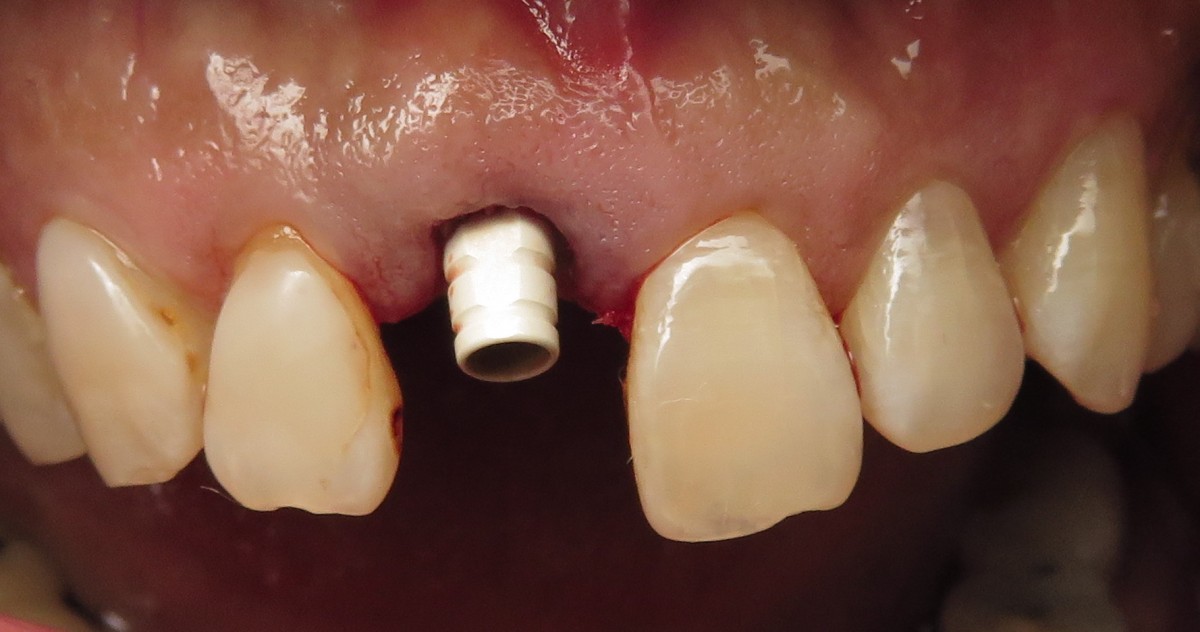

A PEEK provisional abutment was connected to the implant and trimmed (Figure 5) as necessary to allow for a properly positioned and contoured temporary tooth. The screw access was sealed with PTFE, and an acrylic provisional was fabricated using a pre-operative impression and cemented to the abutment using temporary cement. Caution was taken to relieve all centric and excursive/protrusive contacts in order to prevent the premature loading of the implant. The patient was instructed to stay on a soft diet and not to bite with their front teeth.